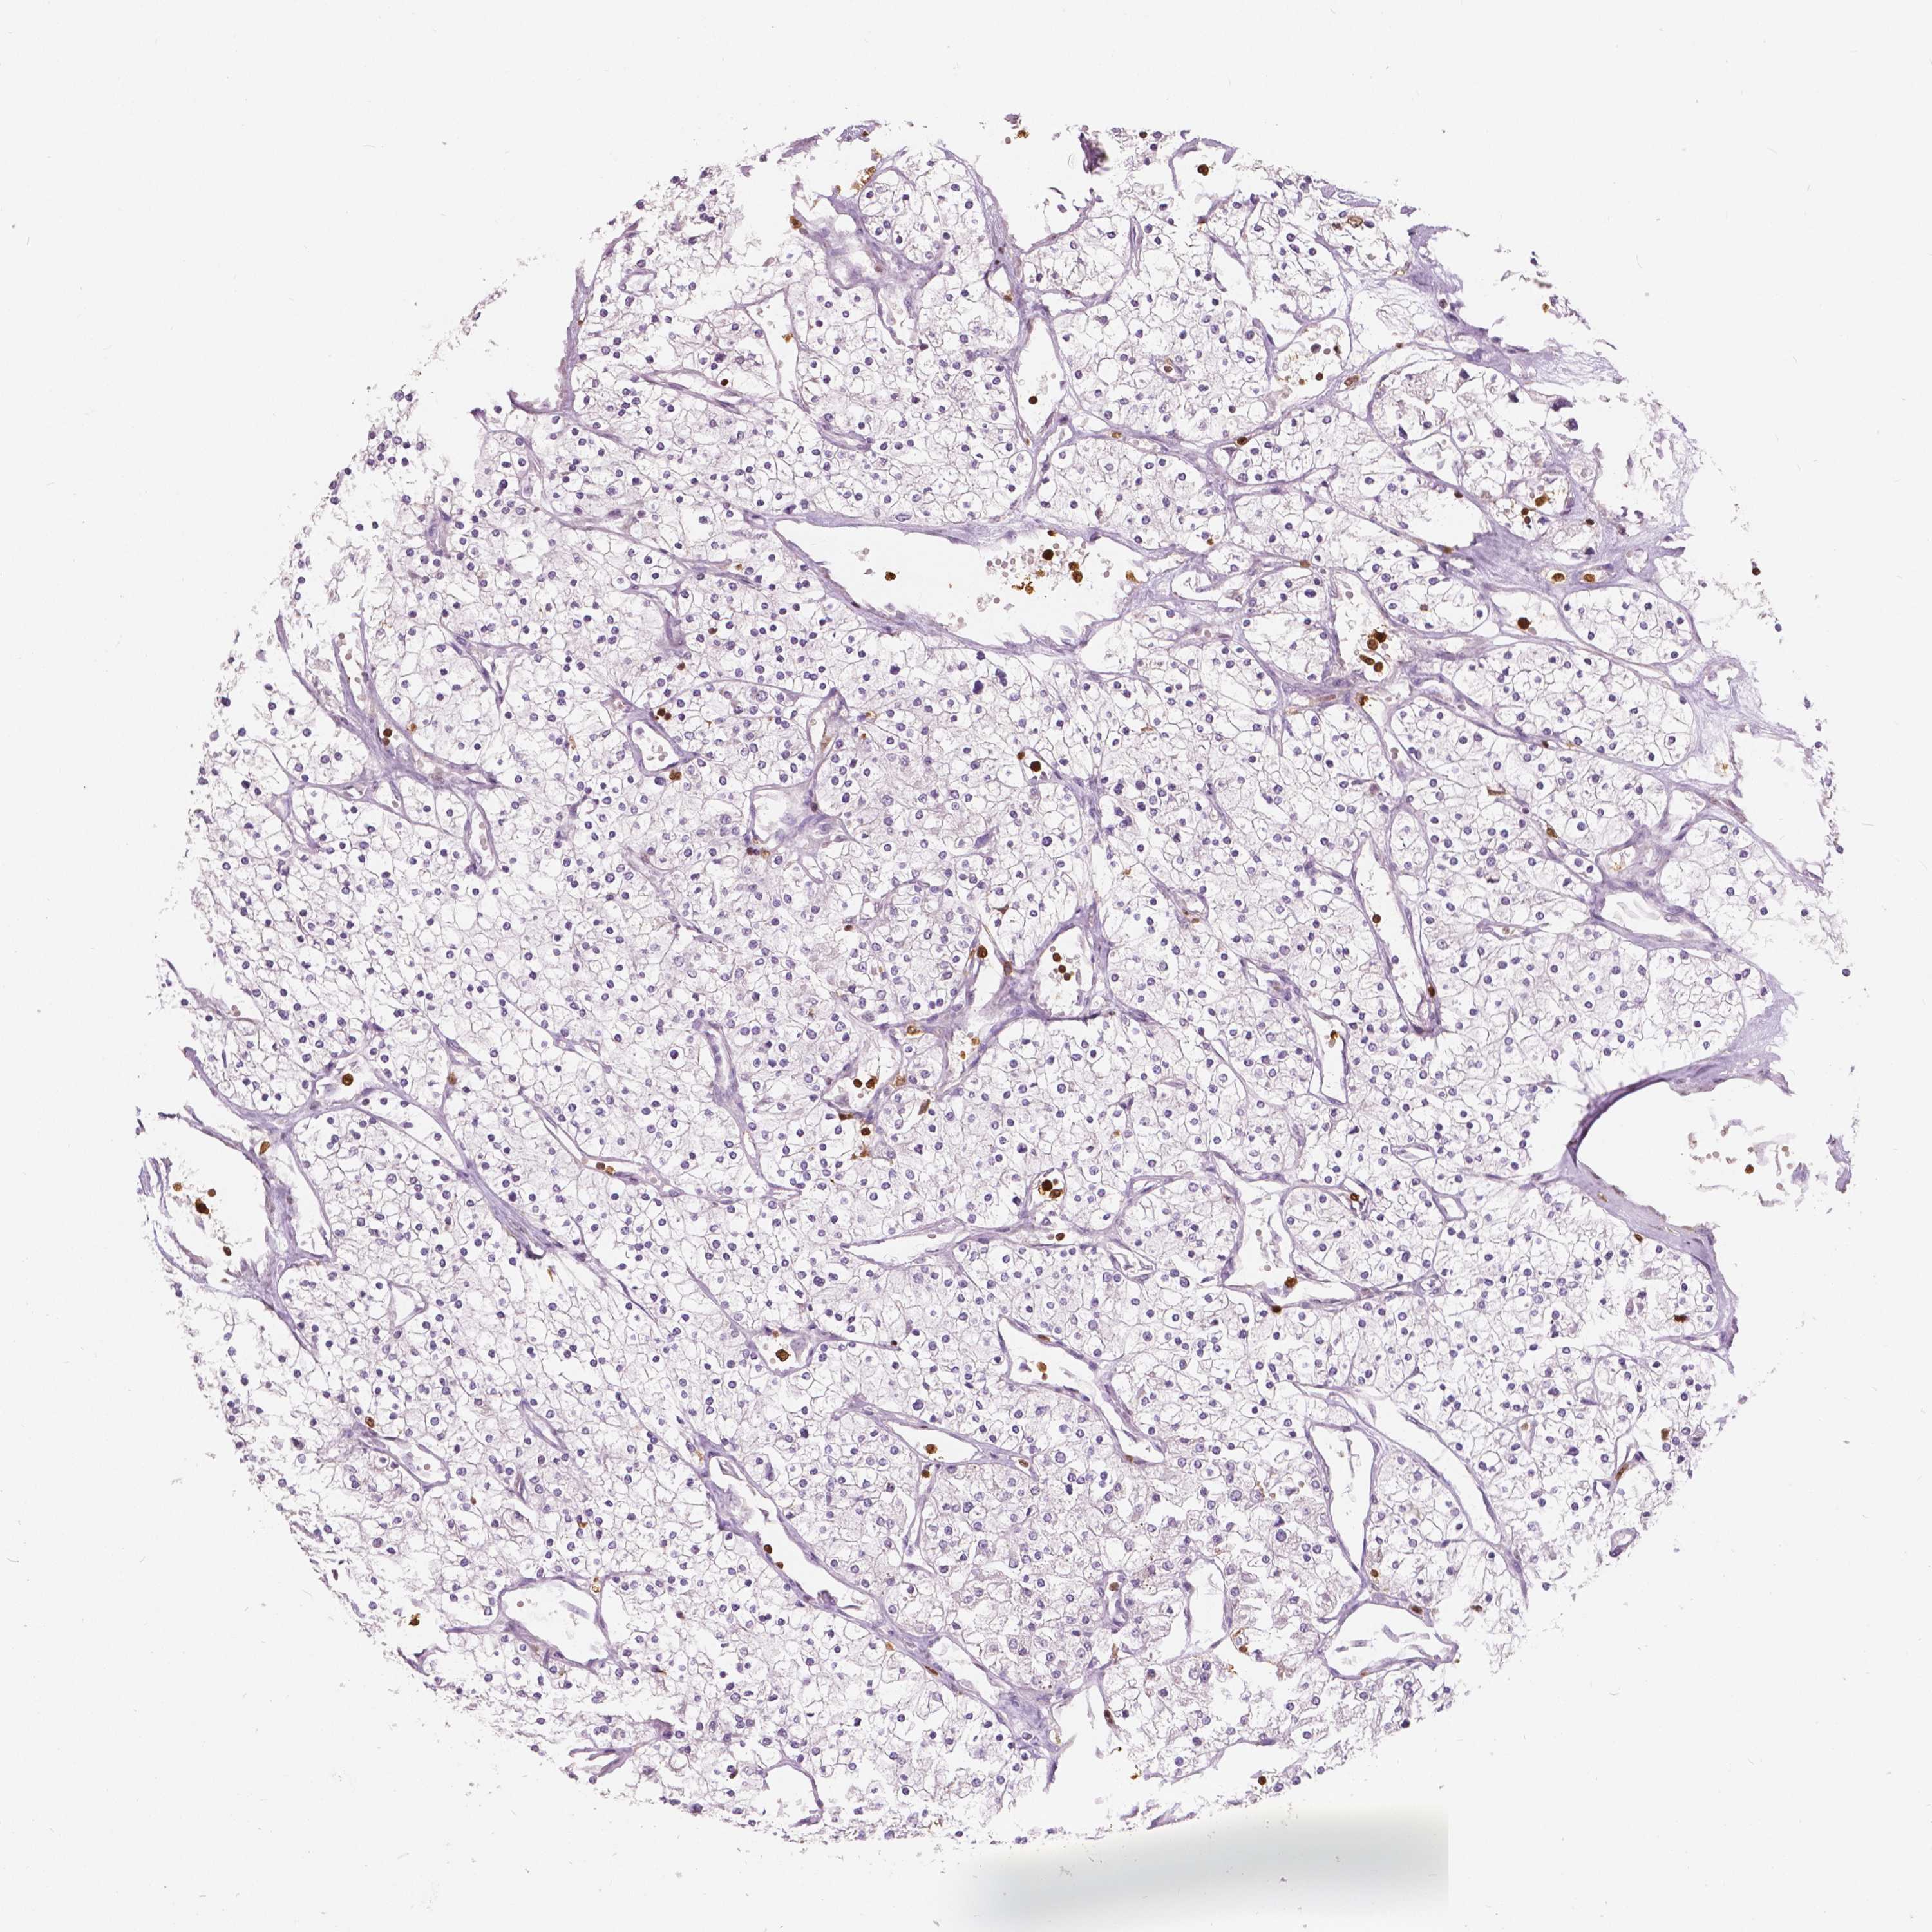

KIDNEY RENAL CLEAR CELL CARCINOMA (TCGA) - Interactive survival scatter ploti

The Survival Scatter plot shows the clinical status (i.e. dead or alive) for all individuals in the patient cohort, based on the same data that underlies the corresponding Kaplan-Meier plots. Patients that are alive at last time for follow-up are shown in blue and patients who have died during the study are shown in red.

The x-axis shows the expression levels (FPKM) of the investigated gene in the tumor tissue at the time of diagnosis. The y-axis shows the follow-up time after diagnosis (years). Both axes are complimented with kernel density curves demonstrating the data density over the axes. The top density plot shows the expression levels (FPKM) distribution among dead (red) and alive patients (blue). The right density plot shows the data density of the survived years of dead patients with high and low expression levels respectively, stratified using the cutoff indicated by the vertical dashed line through the Survival Scatter plot. This cutoff is automatically defined based on the FPKM cutoff that minimizes the p-score. The cutoff can be changed by dragging the vertical line or by entering a cutoff value in the square labeled "Current cut-off".

Under the Survival Scatter plot the p-score landscape (black curve; left axis) is shown together with dead median separation (red curve; right axis). Dead median separation is the difference in median mRNA expression between patients who have died with high and low expression, respectively. It is calculated as follows: median FPKM expression of dead patients with high expression - median FPKM expression of dead patients with low expression. This is intended to aid the user in visually exploring custom cutoffs and the associated p-scores and dead median separation.

Individual patient data is displayed and can be filtered by clicking on one or more of the category buttons on the top of the page. Categories describing expression level and patient information include: high, low, alive, dead, female, male and tumor stages. The scale of the x-axis can be toggled between linear and log-scale by clicking on the "x log" button. Mouse-over function shows TCGA ID, patient information and mRNA expression (FPKM) for each patient.

& Survival analysisi

Kaplan-Meier plots summarize results from analysis of correlation between mRNA expression level and patient survival. Patients were divided based on level of expression into one of the two groups "low" (under cut off) or "high" (over cut off). X-axis shows time for survival (years) and y-axis shows the probability of survival, where 1.0 corresponds to 100 percent.

S100A4 is not prognostic in Kidney Renal Clear Cell Carcinoma (TCGA)

: 214.15

Average pTPM 257.5

Number of samples 521